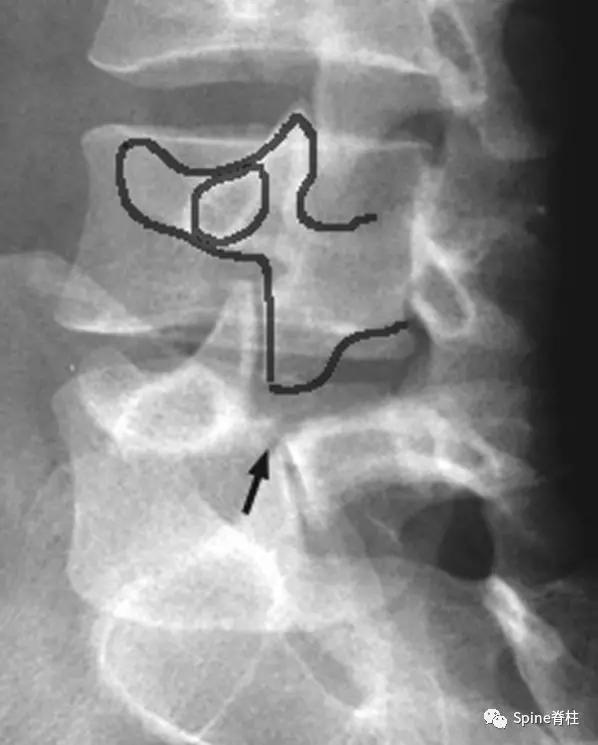

图:腰椎斜位片,图中黑色箭头所示为峡部裂

图:CT所示峡部裂(长箭头),可别认为是棘突骨折